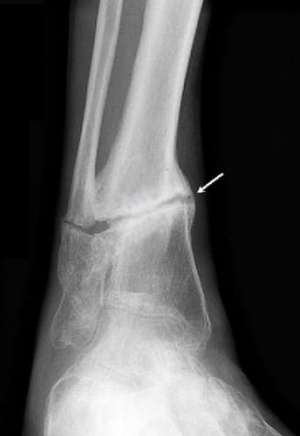

Псевдоартроз плечевой и других костей можно без труда выявить при рентгенологическом исследовании.

Различают два вида ложных суставов — гипертрофический и атрофический. В первом случае при нормальном кровоснабжении начинает избыточно разрастаться костная ткань, однако это приводит только к развитию большого расстояния между отломками.

Второй вид формируется при отсутствии или недостаточности кровоснабжения в месте травмы. Части одной кости соединены между собой соединительной тканью, но к сожалению, она не способна удерживать место перелома в хорошо зафиксированном состоянии.